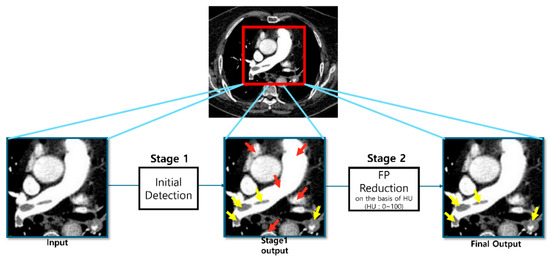

AI-Based Pulmonary Embolism Detection: The Added Value of a False-Positive Reduction Module over a Region Proposal Network

Background: High false-positive rates remain a significant challenge in the automated detection of pulmonary embolism (PE) using Computed Tomography Pulmonary Angiography (CTPA). This study evaluated the additional value of a False-Positive Reduction (FPR) module integrated into a Region Proposal Network (RPN). Methods [...] Read more.

Background: High false-positive rates remain a significant challenge in the automated detection of pulmonary embolism (PE) using Computed Tomography Pulmonary Angiography (CTPA). This study evaluated the additional value of a False-Positive Reduction (FPR) module integrated into a Region Proposal Network (RPN). Methods: A retrospective analysis of 303 CTPA scans (163 PE-positive and 140 PE-negative) was conducted from a single tertiary institution. Both models were additionally validated on an independent external cohort of 100 CTPA scans (50 PE-positive and 50 PE-negative) from the RSNA PE Challenge dataset. The diagnostic performance of the one-stage RPN-only model was compared with that of a two-stage Modified Mask R-CNN (Region-based Convolutional Neural Network) incorporating the FPR module. Results: The Modified Mask R-CNN exhibited significant improvement in terms of specificity. The false-positive rate per scan decreased by 31% in comparison to the RPN-only model. Although there was a slight reduction in patient-level sensitivity, the Positive Predictive Value significantly increased by 10.5%. Additionally, patient-level specificity for emboli with a volume ≥ 1000 mm3 increased, reflecting a 7.4% relative improvement in detecting clinically significant emboli. Conclusions: The Modified Mask R-CNN significantly reduced false positives while maintaining high sensitivity over a region proposal network. Full article